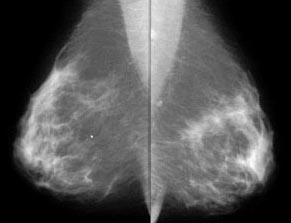

mammo breast CA